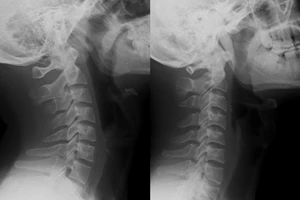

Bệnh nhân được chẩn đoán ngộ độc paracetamol do uống quá liều loại thuốc này. Ảnh: BVCC